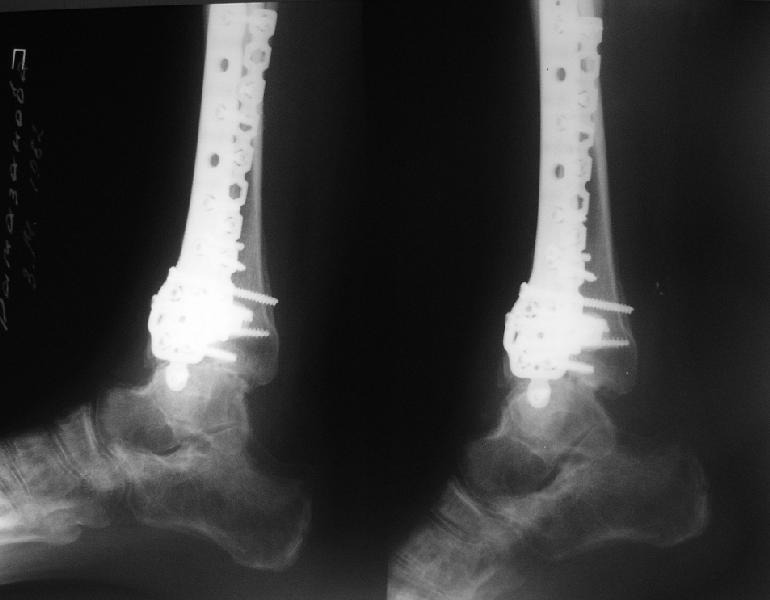

Dear коллеги,Обратилась женщина, 25 л. 8 мес. назад в одной из больниц сделан остеосинтез пилона. На сегодня ходит без дополнительной опоры, хромая на поврежденную ногу. Движения в голеностопном суставе еще есть. Снимки в приложении.

A female, 25, 8 month ago operated elsewhere. To date walks without support with pain and limp. The ankle is mobile yet. Images attached.The question is what to do now? The patient is not very keen on ankle fusion (though likely could change her mind if necessary)Is it worth to try a reconstruction procedure and what kind? Maybe it allows to restore alignment and tibio-fibular relationship - will it provide painless limb for more or less significant time?Or just remove the hardware and leave her alone until she herself comes for fusion?

She has an intraarticular screw on CT, best is to remove all and wait untill she asks for fusion.

CT images/xrays confirm incongruity of articular surfaces as well as intraarticular screws.

removing just those screws which have penetrated the joint may take some pain away.